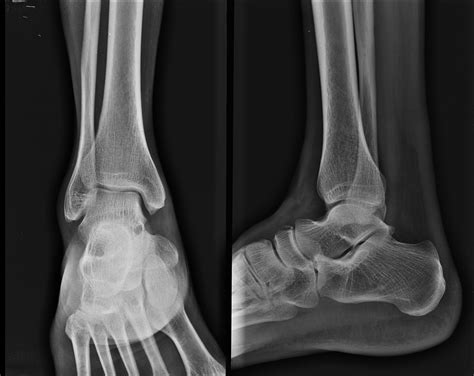

X-ray Imaging Primary scan to identify major breaks or displacement.

Because a scaphoid bone fracture does not always appear on an initial X-ray, doctors often rely on clinical examination and follow-up imaging. If a doctor suspects a fracture despite clear X-rays, they may immobilize the wrist and order repeat imaging in one to two weeks. During this time, the fracture line often becomes more visible as the bone begins to resorb.